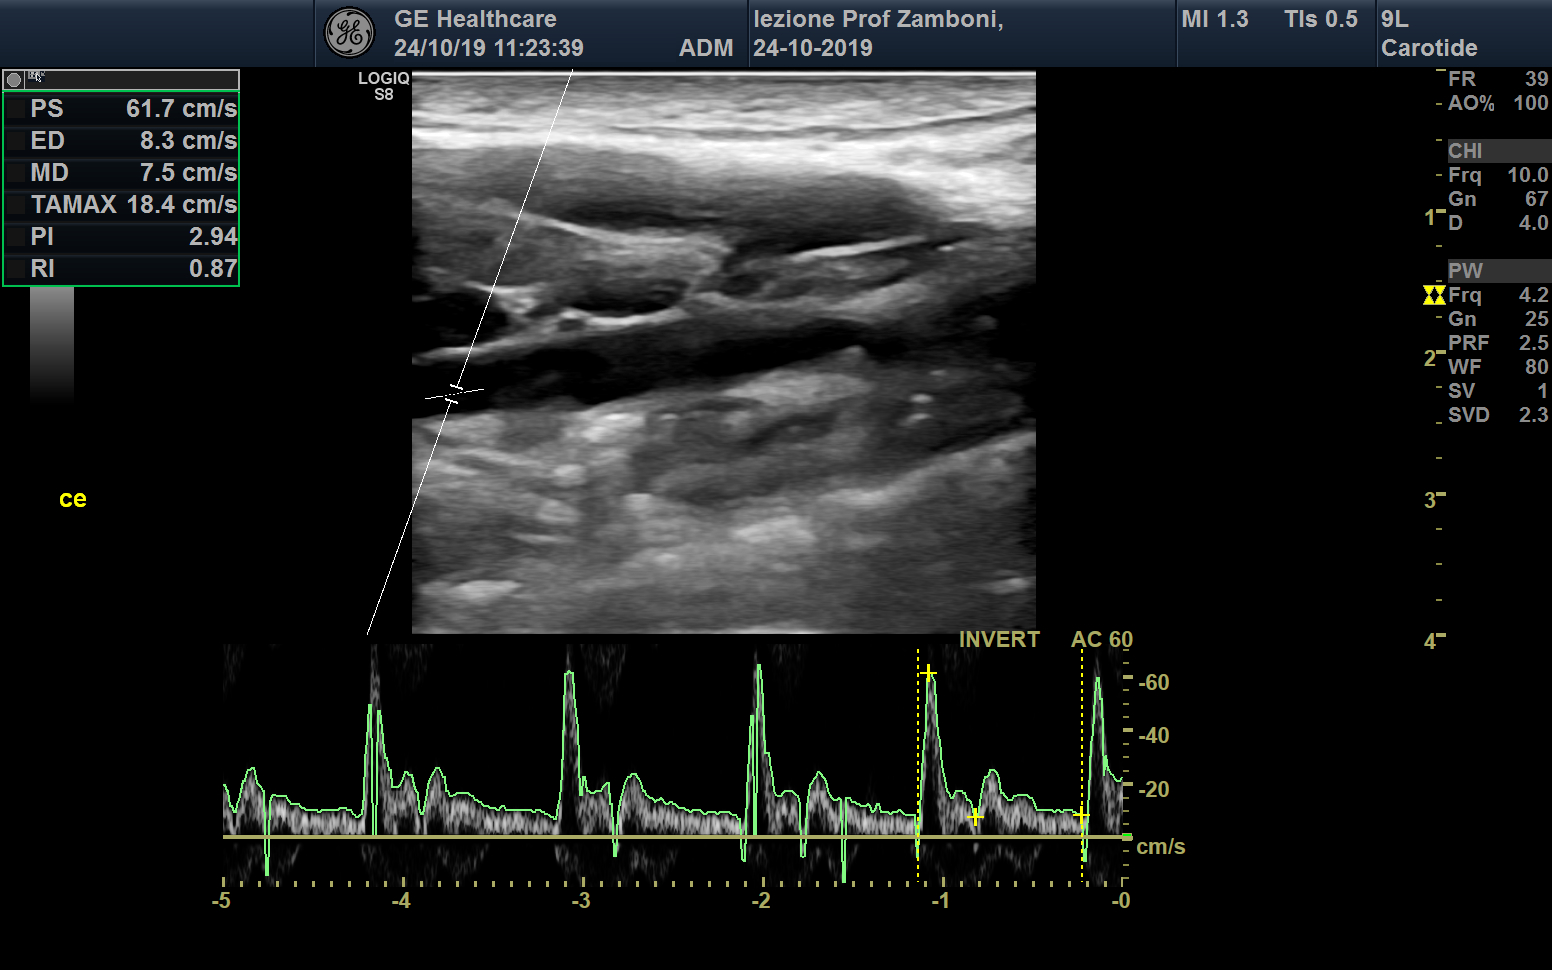

PW Carotide esterna

JPEG image icon PW Carotide esterna.jpg — JPEG image, 580 kB (594337 bytes)